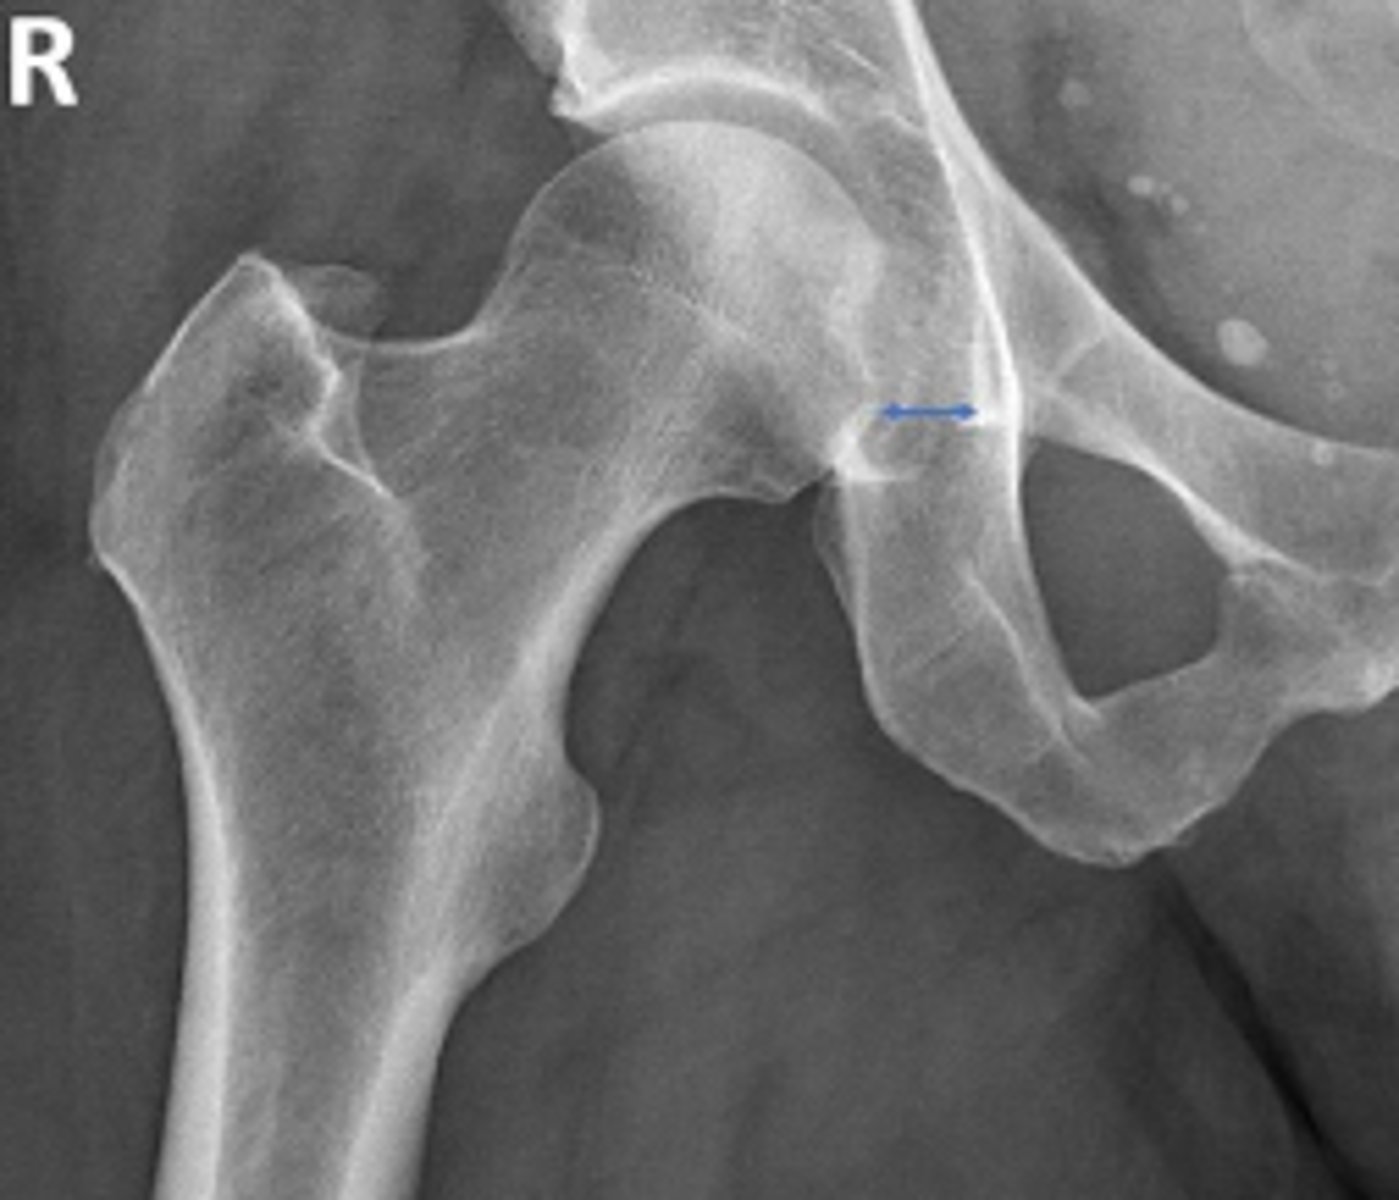

Teardrop distance

What is the name of the assessment?

6-11mm

What is the normal range for this assessment?

The distance between the most medial margin of

the femoral head and the adjacent pelvic

teardrop

What are the osseous landmarks for this assessment?

Yes (normal is 6-11mm)

Is the measurement within normal limits?

Femoroacetabular joint inflammation

Name 1 condition that may result in a measurement of 15mm?

AP pelvis and AP hip views

Name 2 radiographic views for this assessment?

Late stage degenerative joint disease

Protrusio acetabuli

Name 2 conditions that may result in a measurement of 3mm?

Waldenstrom's sign

What is the named sign if this assessment has a value > 2mm difference

between the left and right side?